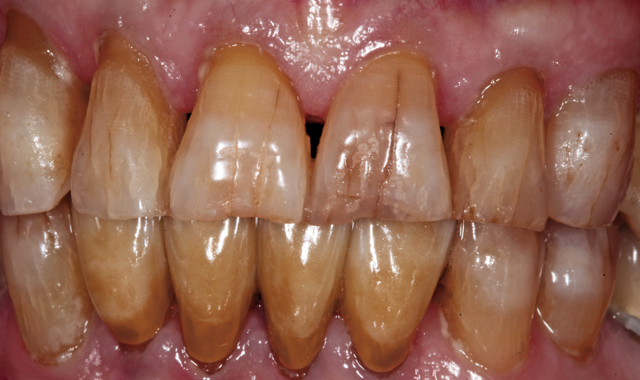

The patient then returned for final try-in and cementation of the definitive CAD/CAM restorations. Because the patient was directly involved in the diagnosis, evaluation, smile design, treatment planning and provisionalization evaluation-and because the final restorations were designed based on digital replicas of the approved

provisionals-there were no unanticipated results. In fact, no adjustments were needed to the contacts or occlusion, and the patient approved the esthetics. The splinted crowns were then cemented with resin reinforced glass ionomer cement (Figs. 21 and 22).